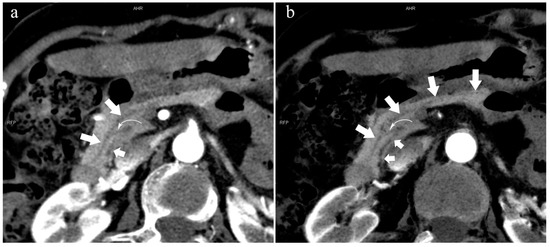

There were 121 patients with AP in the two groups. In the variant group, a total of 27 patients had AP (22%, 27/121), of which the incidence of type 3c (33.3%, 9/27) and type 4a (18.5%, 5/27) are higher. There were 18 patients with CP, of which six patients (33%, 6/18) were in the variant group. Patients with autoimmune pancreatitis (AIP) only existed in the normal group (n = 4).

5.3.2. Pancreatitis

Kensuke Takuma et al. [27] suggested that complete PD may be the etiology of AP, CP, and dorsal pancreatic cancer. An important factor of complete PD promoting these diseases is dorsal pancreatic duct obstruction. We considered that, in type 4, only the dorsal pancreatic duct drains the pancreatic juice to the MiP. However, the MiP easily accumulates and stagnates due to the small physiological opening, which may lead to pancreatitis [40,41]. In this study, there were significant differences between AP (Figure 4), CP, and complete PD.

In the variant group, the incidence of AP in patients with type 3c was considerably higher than that in type 3a. Type 3c, also known as “reverse pancreas divisum”, does not communicate with the MPD but is open to the MiP, while type 3a is the opposite. In type 3c, there is a “vacuum” area between the MPD and ADP that may not be communicated, while type 3a cannot be drained directly by the MiP, but most areas can be drained indirectly by entering the MPD. This may be a reasonable explanation for this phenomenon. Table 4 also confirms our point of view. The frequency of type 2 was 2.4%, and AP accounted for 26% of type 2, which may have also been caused by the small orifice of the MiP drainage and the poor secretion flow [40,41].